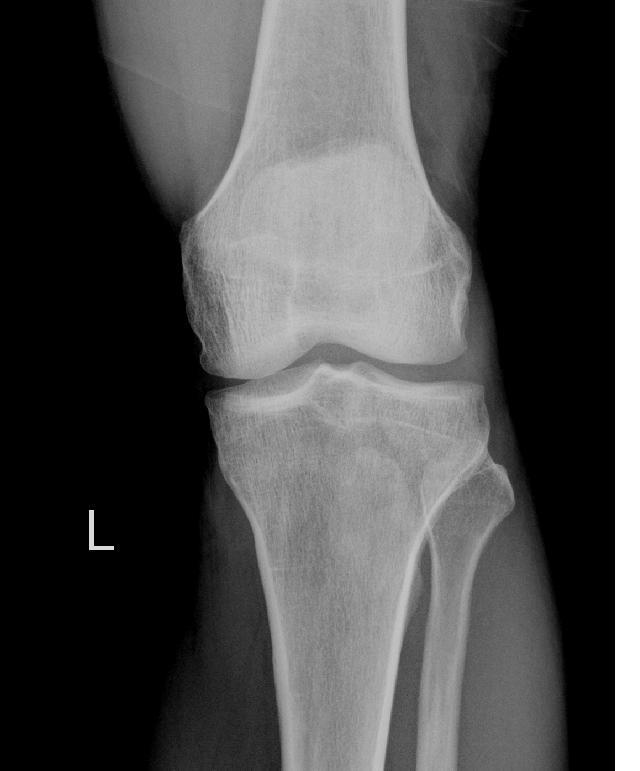

标题: X2880:胫骨结节前方的小骨是什么?

会不会是副髌骨???其内似可见骨小梁,如果是钙化可能不会有骨小梁吧??疑问中……

胫骨结节骨软骨炎

没融合的骨骺.或膑韧带钙化.

应该是副骨

是多个骨化中心在发育过程中没有合并所导致

完全可以排除髌韧带钙化.考虑发育原因或以前有过胫骨结节骨软骨炎病史.

考虑发育原因或以前有过胫骨结节骨软骨炎病史.

髌韧带钙化,考虑以前患过胫骨结节骨软骨炎

软组织骨化,髌韧带骨化可能性大。

应该是胫骨结节骨软骨病 可以双侧对比

没融合的骨骺

二次骨化中心未融合.~